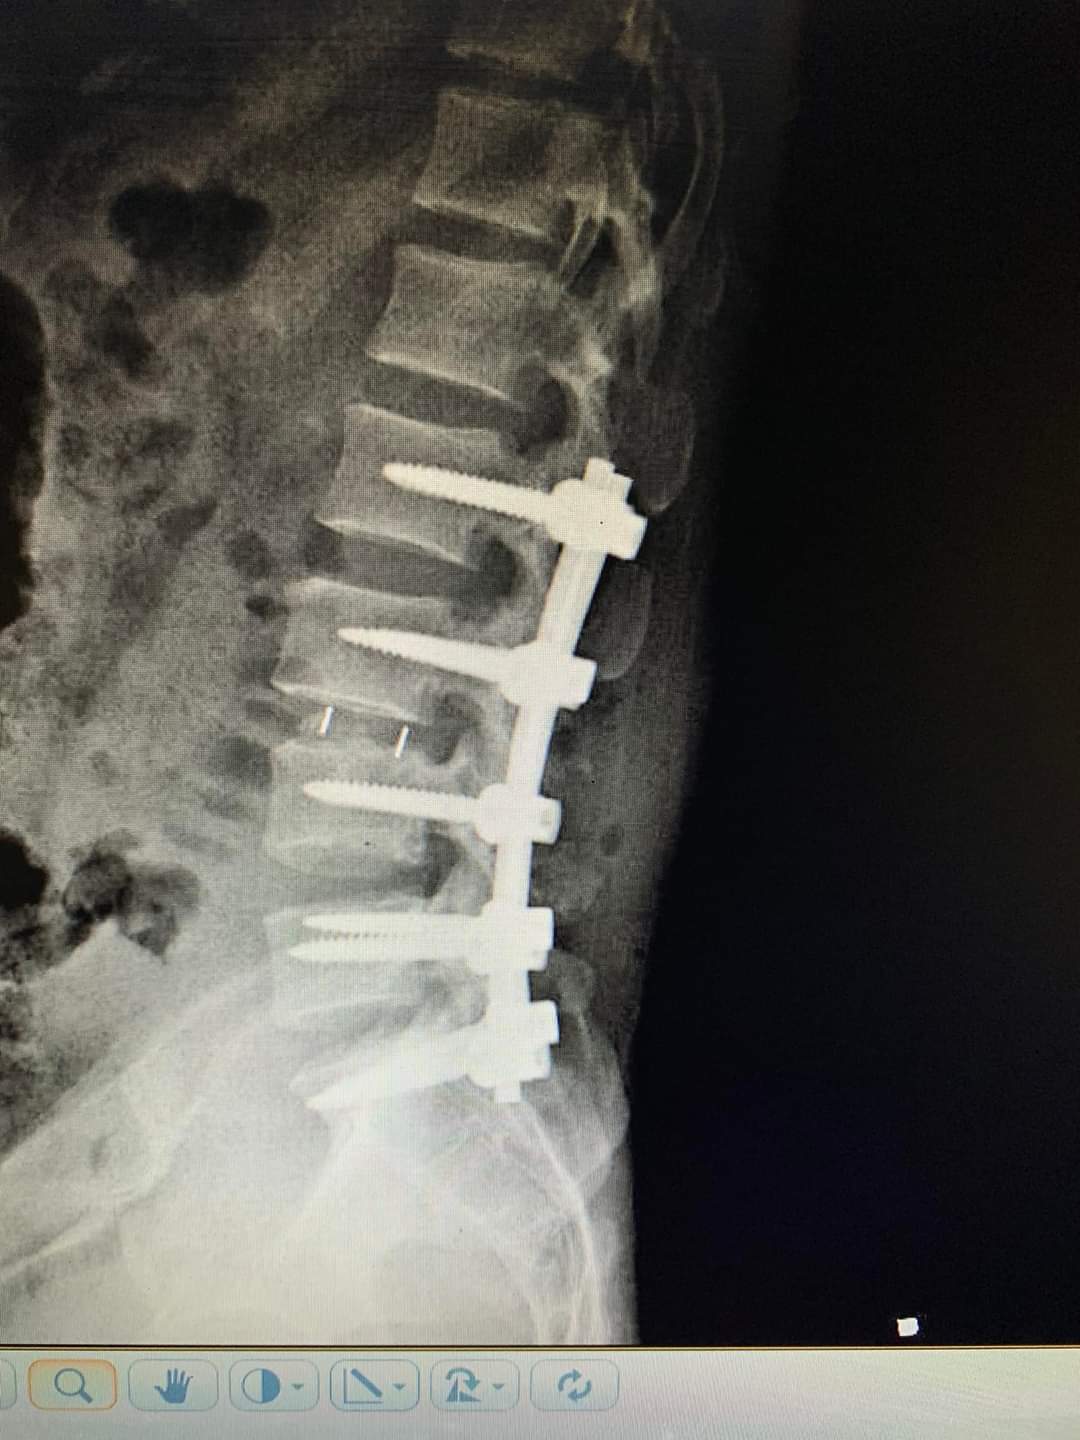

Các bác sĩ của khoa Ngoại cột sống cùng ê kíp gây mê của khoa Phẫu thuật Gây mê hồi sức đã tiến hành nắn chỉnh trật, giải phóng chèn thần kinh, hàn liên thân đốt bằng đĩa đệm, xương ghép và nhiều nẹp vít chuyên dụng cho cột sống. Sau hơn 5 giờ đồng hồ phẫu thuật, bệnh nhân được hồi tỉnh an toàn tại khoa Phẫu thuật Gây mê hồi sức và chuyển về lại khoa Ngoại Cột sống theo dõi điều trị, chăm sóc tiếp tục.

Cột sống của bệnh nhân được cố định bằng nẹp vít chuyên dụng.